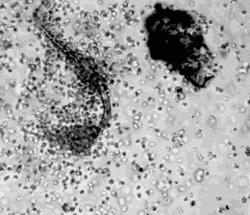

寄生虫

潮湿温润的菊部地区是滋养寄生虫的风水宝地,尤其是蛲虫。 蛲虫是一种肠道寄生虫,寄生于人体的回盲部,以盲肠、阑尾、结肠、直肠及回肠下段多见。

当你睡着以后,肛门括约肌也松弛了下来,部分雌虫就会趁机爬出肛门,在附近皮肤产卵,这可能就是你晚上菊花很痒的缘由。